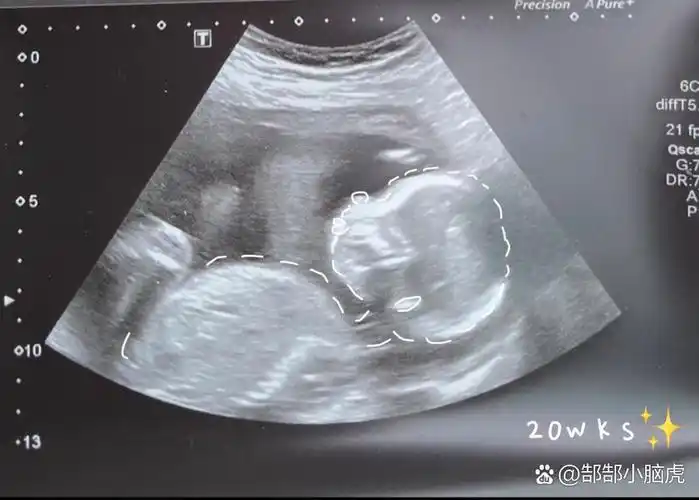

001 20周的宝宝b超图怎么这么圆

怀孕第20周:胎儿身体的变化